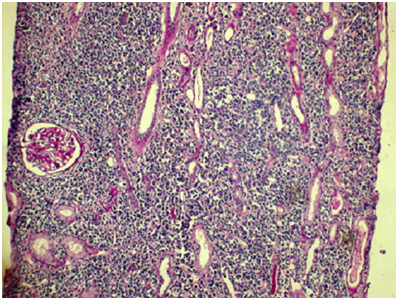

Non-Hodgkin lymphoma/leukemia and Hodgkin’s disease pathology correlations

NHL/CLL cases were complicated by PGNMID, MN, SI (Figure 10), TIN, DNS and AA amyloidosis; HD-by MCD, FSGS and AA.

Figure 10 Lymphoid infiltration, PAS x 100.